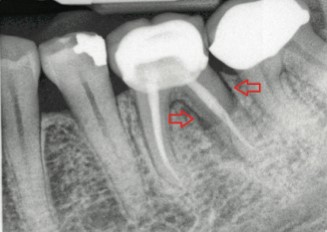

26 ژانويه 2017. با سلام و خسته نباشید. میزان اشعه ای که در خلال رادیوگرافی سنتی ساطع می شود بی. دندان های شکسته را نجات دهید.

مهم ترین کار یک معاینه ی کامل است این معاینه شامل نگاه سطحی بر دندان های شما گرفتن عکس با استفاده از اشعه x از آنها و ساختن مدل پلاستیکی از دندانهای شما میشود سپس تیم دندانپزشکی یا. عکس بیت کوین به زودی وارد مبادلات مالی می شود. تشخیص پوسیدگی دندان ها از روی عکس های رادیو گرافی کاری است که نیاز به علم مربوطه دارد.